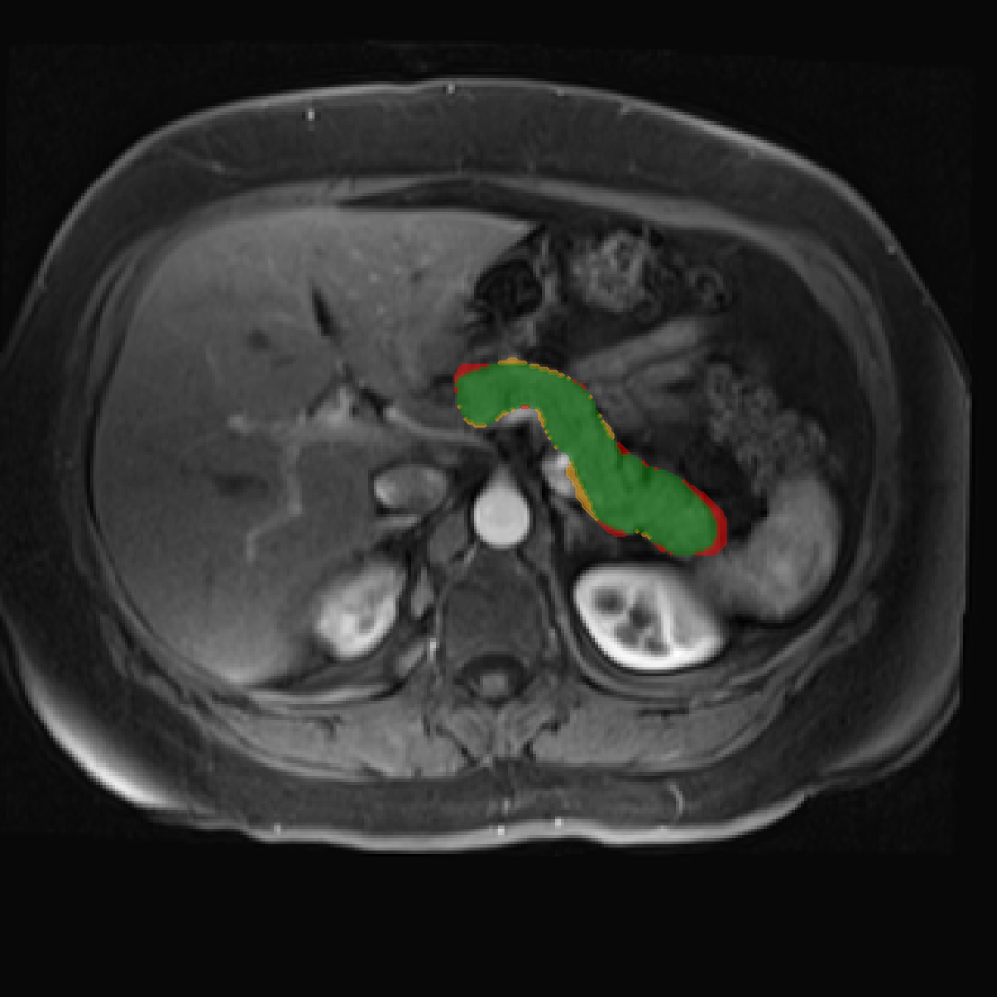

Accurate pancreas segmentation is a critical prerequisite for precise cyst analysis and classification. Recently, we developed PanSegNet [zhang2025large], a novel segmentation architecture incorporating linear self-attention layers [zhang2022dynamic] within the nnUNet framework [isensee2021nnu] to enhance global information modeling capabilities while maintaining computational efficiency (Fig. 1). PanSegNet demonstrated exceptional segmentation performance across both T1W and T2W modalities, achieving mean dice scores of 86.817.30% and 89.626.38%, respectively (Table 1, Fig. 2b-c). This performance significantly exceeded that of Swin-UNETR [hatamizadeh2021swin], one of the most used state-of-the-art transformer-based medical segmentation models, which achieved dice scores of 79.091.40% and 76.290.66% for T1W and T2W, respectively (). In this study, we integrated PanSegNet into our Cyst-X engine along with a classifier for risk prediction. In Section 2.2, we show that the choice of segmentation model affects the classification results. The performance advantage of PanSegNet was consistent across all seven medical centers, demonstrating robust generalization despite variations in imaging protocols and equipment (Table 1). This cross-institutional reliability is particularly important for clinical applications, where model performance must remain consistent regardless of imaging site or acquisition parameters.

Each patient was categorized into one of these three ground truth classes: no risk/control, IPMN low-risk, or IPMN high-risk. To evaluate variability in image acquisition, we applied uniform manifold approximation and projection (UMAP) to image quality indicators, revealing distinct clustering patterns by imaging center and slice thickness. This heterogeneity reflects real-world clinical variability, enhancing the dataset’s generalizability while presenting technical challenges for model development. Fig. 6 shows examples of low-grade, high-grade, and cancer developing IPMNs from the Cyst-X dataset.